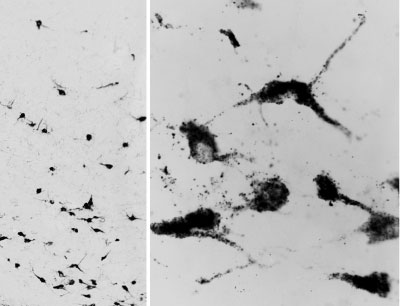

APR12655G (0.05 μg/ml) staining of PFA-perfused cryosection of Human Hypothalamus. Antigen retrieval with citrate buffer pH 6 at 80C for 30min, HRP-staining with Ni-DAB after Biotin-SP-antigoat amplification. Data obtained by Prof. Erik Hrabovszky, Inst, Exp, Med., Budapest, Hungary. |